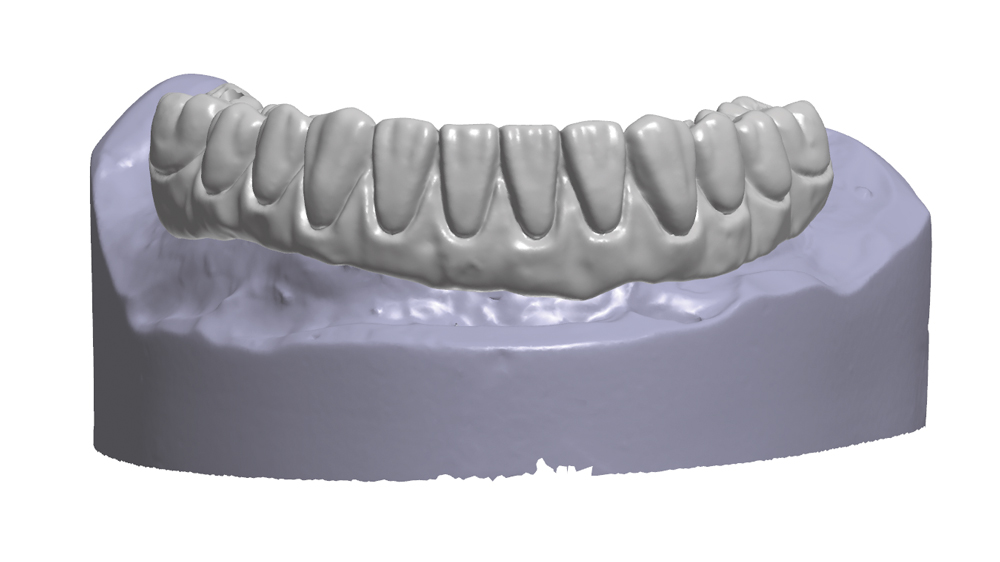

Once osseointegration is complete, the BruxZir® Full-Arch Implant Prosthesis is the ideal choice for the restoration, as its monolithic construction prevents chips, stains, breakage, and dislodged or worn-down prosthetic teeth.3,4 This treatment option has helped elevate the quality of care I’m able to provide for my edentulous patients, who no longer return to my office with a broken acrylic appliance in hand.

The following case demonstrates how to immediately place implants in full-arch indications. By properly positioning the implants, maximizing primary stability and providing the most durable restoration possible, the short- and long-term needs of the patient are addressed in an efficient, predictable manner.